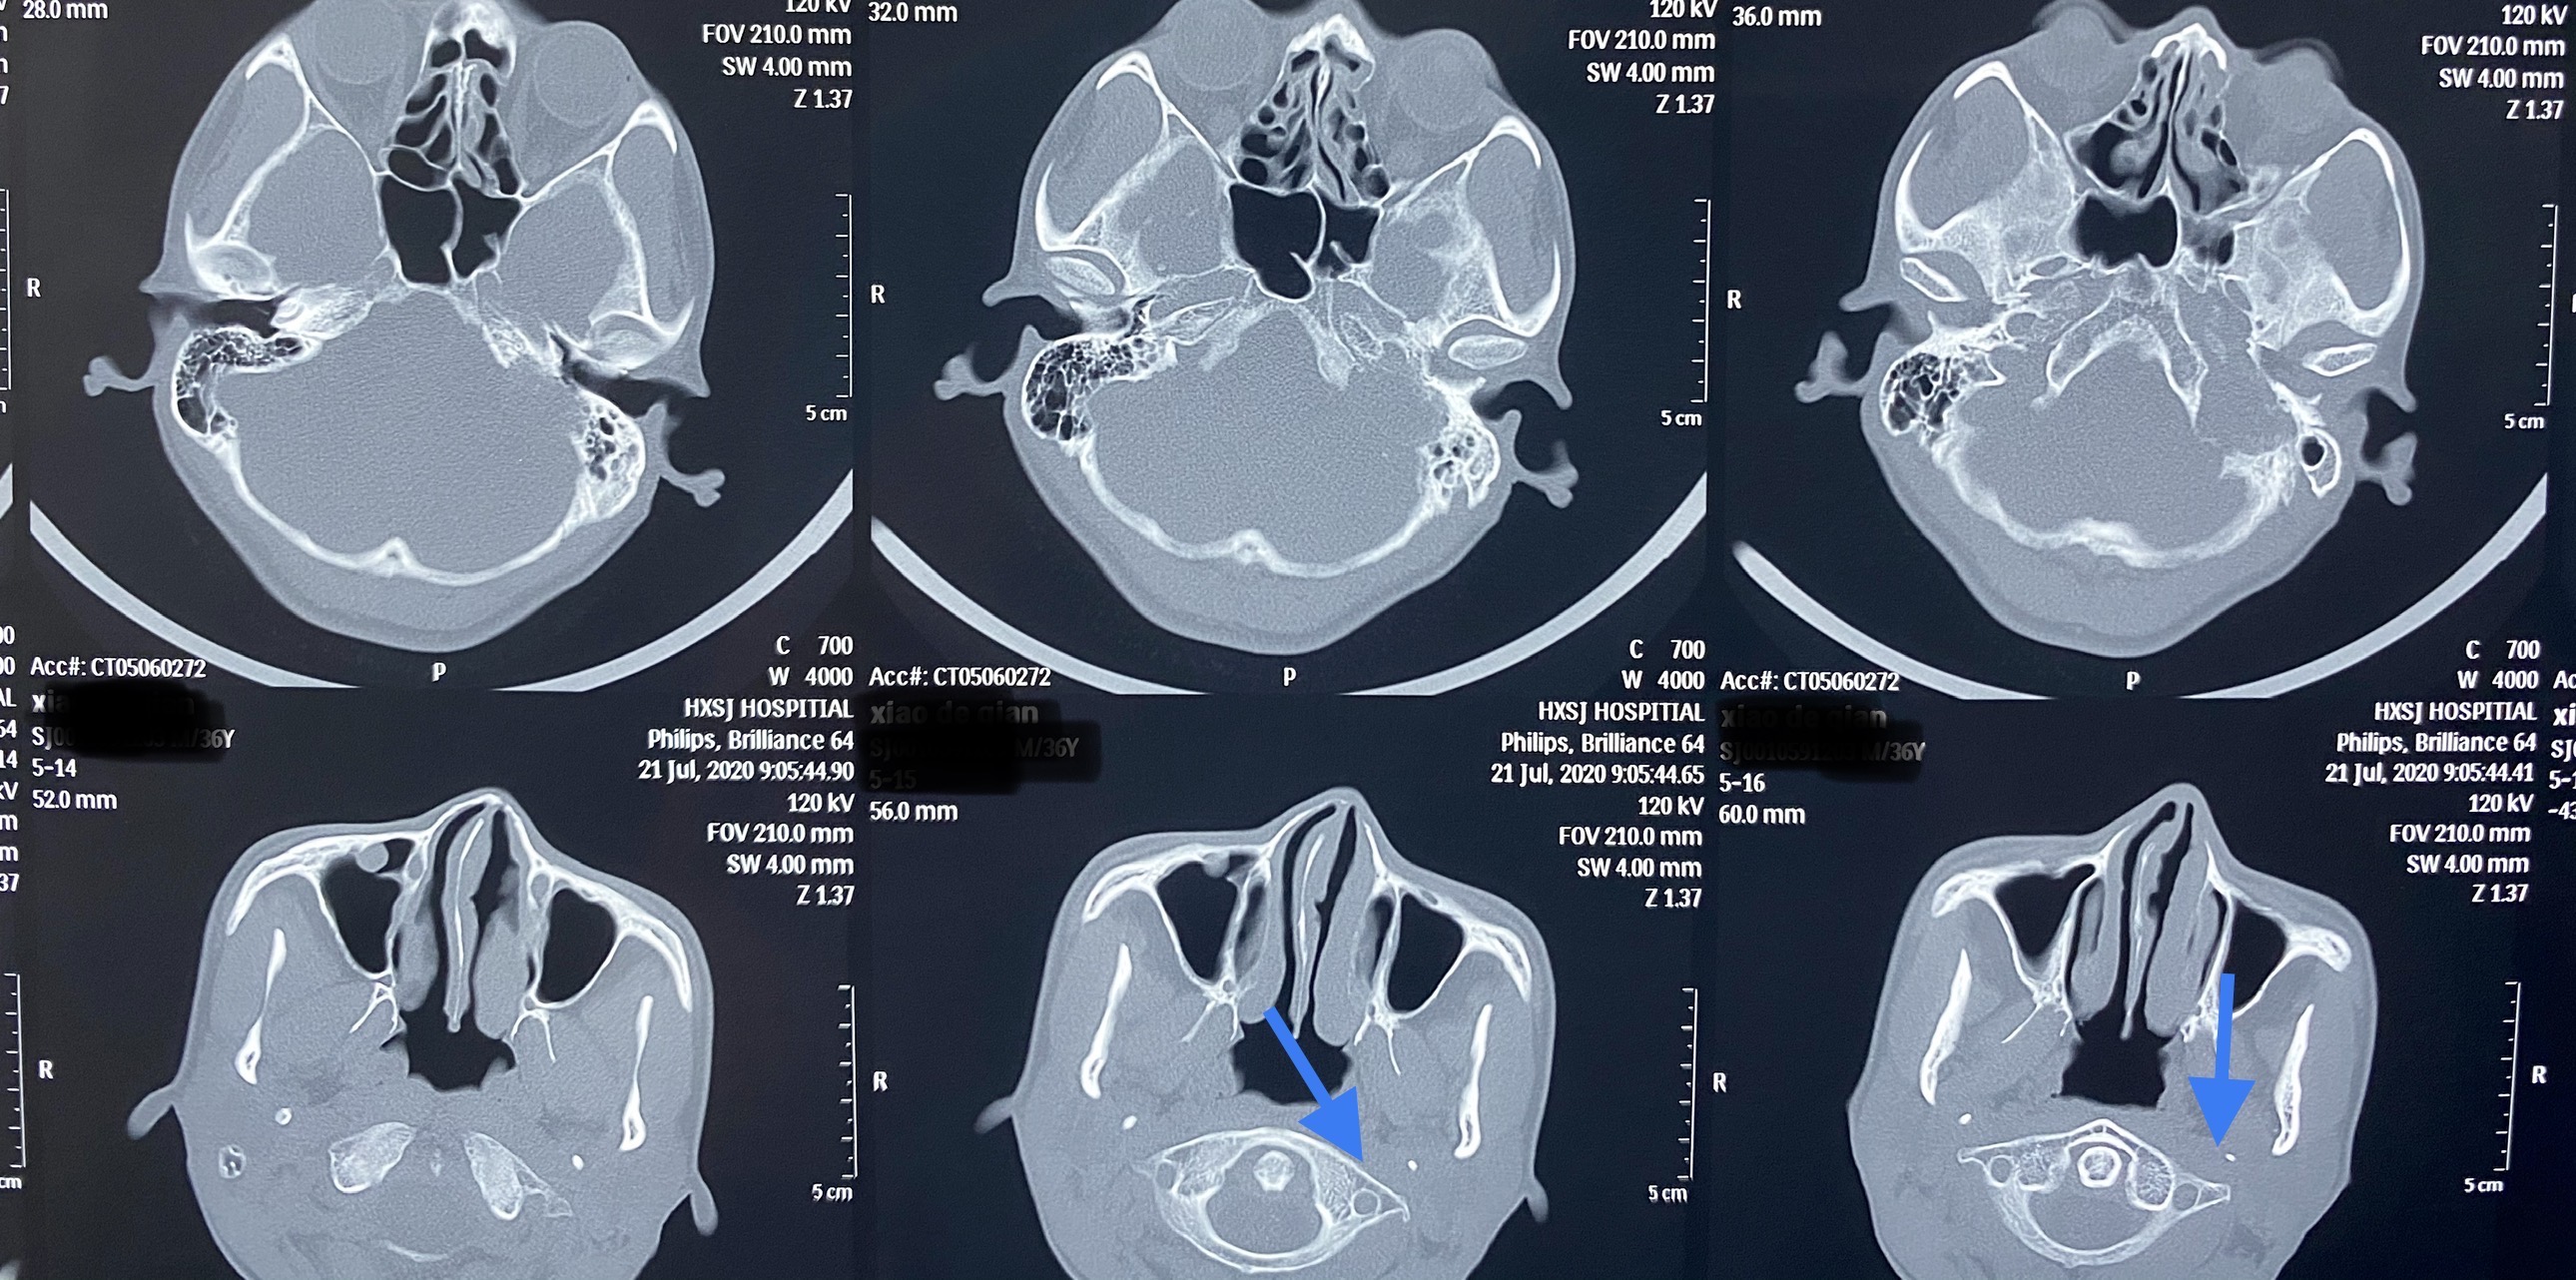

蓝色箭头指出C-1横突阻挡位于其前方的部分瘤体

图中:1、乳突尖 2、椎动脉 3、颈内动脉 4、颈外动脉 5、迷走神经 6、副神经 7、颈内静脉 8、面神经 9、C-1横突